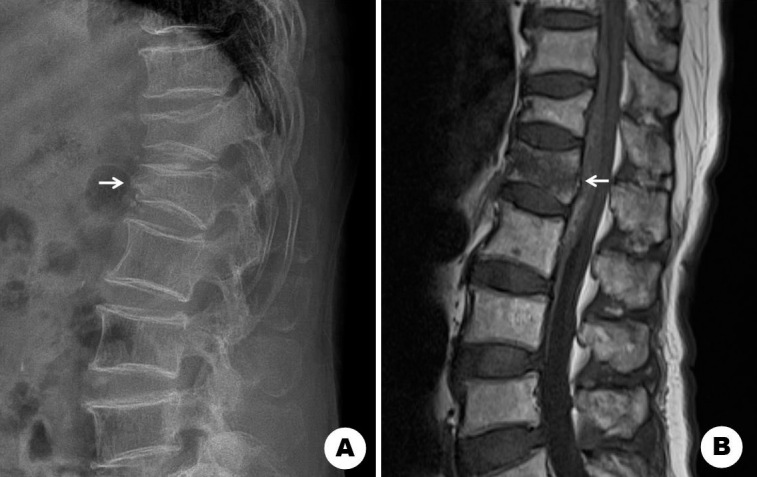

Complete Resolution of Hematoma after Vertebroplasty in Epidural Hematoma Associated with Acute Osteoporotic Vertebral Fracture: A Case Report.

急性骨质疏松性椎体骨折伴硬膜外血肿椎体成形术后血肿完全消退1例报告。